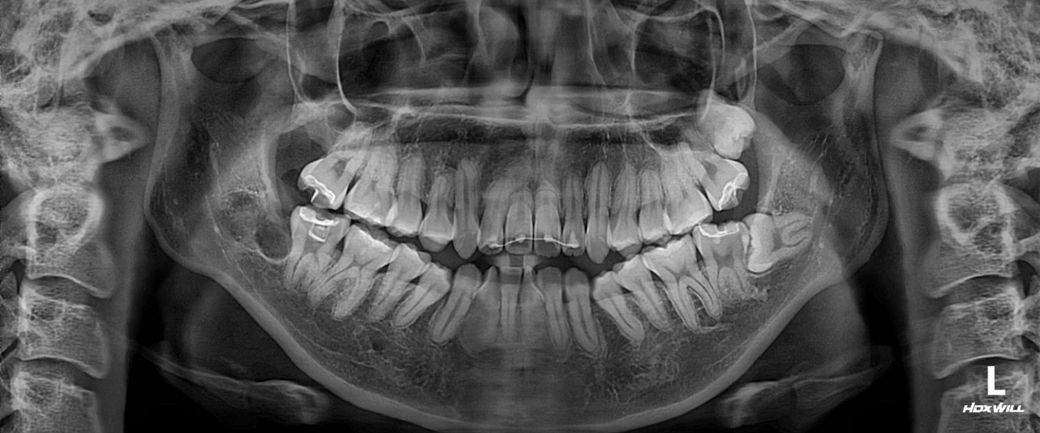

윗 앞니 두개 뿌리가 짧아서 고민이 되네요

현재 구강 내 사진이 필요하기는 하나 올려주신 파노라마 사진으로 보았을 때는 교정 시 앞니 뿌리가 짧아서 결국에는 문제가 생길 가능성이 큽니다. 따라서 추후 치료 계획을 가지고 시행하는 것이 좋으며 나중에 앞니를 못쓰게 되면 다시 임플란트를 해라고 하는 것은 도중에 치료 계획이 바뀌는 것이기 때문에 대학병원에서 이미 이를 예측하고 세운 교정 계획을 따라 시행하는 것이 가장 맞아 보입니다. 미리 계획을 세워놓아야 추후 나타날 수 있는 부작용 등을 효과적으로 대처할 수 있습니다.